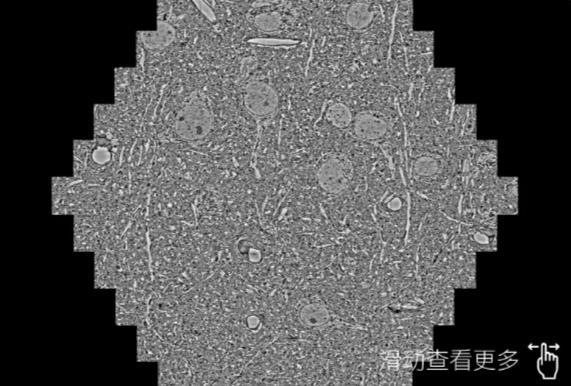

鼠脑切片。左图使用安阳蔡司安阳扫描电镜MultiSEM706对165μmx143pm面积区域成像,耗时仅需1.5秒。右图为鼠脑切片中30μm区域放大效果。样品由芝加哥大学B.Kasthuri提供。

使用蔡司高速安阳扫描电镜MultiSEM对1mm²人脑皮层组织进行高分辨成像,并对其中的各种细胞结构进行三维重构分析。左图展示了2x3mm²组织平面中锥体神经元的三维重构效果。右图显示了局部体积神经元三维重构。图像由哈佛大学chtman实验室提供,渲染图由D. Berger 制作。